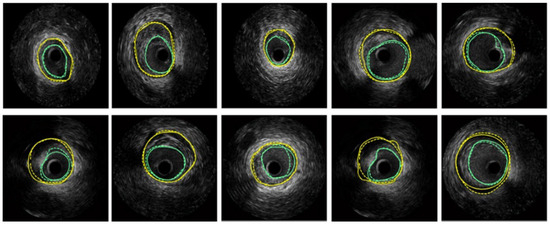

- Xia, M.; Yang, H.; Qu, Y.; Guo, Y.; Zhou, G.; Zhang, F.; Wang, Y. Multilevel structure-preserved GAN for domain adaptation in intravascular ultrasound analysis. Med. Image Anal. 2022, 82, 102614. [Google Scholar] [CrossRef]

| MSP-GAN | Preserves intravascular structures during domain adaptation, uses transformers for global pathology information preservation | Complex architecture, may require large amounts of data for training | Ensures local structures correspondence between source and translated images | IVUS domain adaptation |